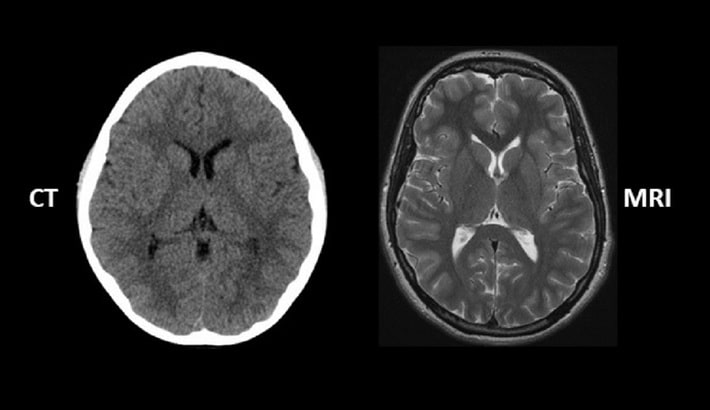

وقتی صحبت از بررسی دقیق مغز میشود، معمولاً دو روش اصلی در تشخیص استفاده میشود: سیتی اسکن مغز و امآرآی مغز. هر دو روش تصویربرداری پیشرفته هستند، اما در نوع نمایش بافتها، میزان دقت و کاربردهای تشخیصی تفاوت دارند. در ادامه به صورت کامل و ساده توضیح میدهیم که هرکدام چه مزایا و محدودیتهایی دارند؛ همچنین در چه شرایطی، پزشکان یکی را بر دیگری ترجیح میدهند.

در سی تی اسکن مغز از پرتوهای ایکس استفاده میشود تا از زوایای مختلف از سر تصویر گرفته شود. سپس کامپیوتر این تصاویر را به صورت مقاطع سهبعدی بازسازی میکند؛ همچنین ساختار مغز، استخوان جمجمه، عروق و فضاهای پر از مایع را نشان میدهد.

اما امآرآی مغز (MRI) بر پایهی میدان مغناطیسی و امواج رادیویی کار میکند و هیچگونه اشعهای در آن استفاده نمیشود. این روش جزئیات بسیار بیشتری از بافتهای نرم مغز، مانند ماده خاکستری، سفید و حتی تومورها را نشان میدهد.

دقت سی تی اسکن مغز در برابر امآرآی

اگر بیمار دچار ضربه مغزی یا خونریزی ناگهانی در مغز شود، پزشکان معمولاً در مرحله اول از سی تی اسکن مغز استفاده میکنند. چون این روش در مدت زمان کوتاه (کمتر از ۵ دقیقه) میتواند خونریزی، شکستگی جمجمه یا وجود لخته را با دقت بالا نشان دهد. در موارد اورژانسی، سرعت سیتی اسکن مزیت اصلی است.

دقت در بررسی بافتهای نرم مغز

در مقابل، امآرآی مغز برای بررسی بافتهای داخلی و تغییرات ظریف مغزی، بسیار دقیقتر عمل میکند. مثلاً برای تشخیص:

در این موارد، امآرآی میتواند نواحی بسیار ریز و تغییرات جزئی در بافتها را نشان دهد که در سیتی اسکن معمولاً قابل مشاهده نیستند.